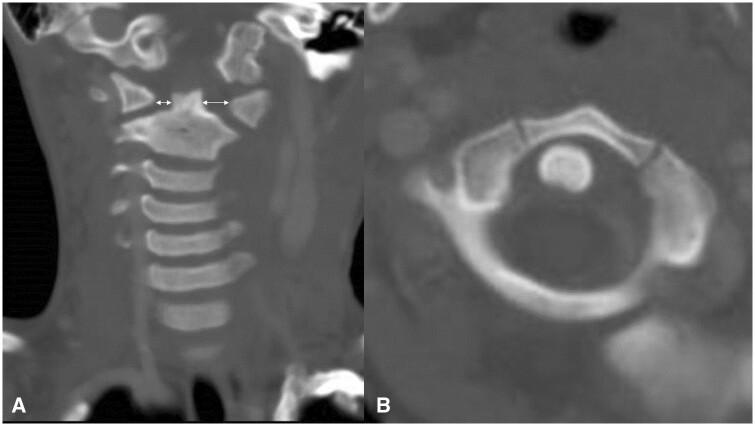

Various respiratory, musculoskeletal, gastrointestinal, neurological, and urinary complications have been reported in Kawasaki disease. Here, we describe a rare case of atlantoaxial rotatory fixation (AARF) associated with incomplete Kawasaki disease. The case is of a healthy 4-year-old Japanese boy who had a high-grade fever, lymphadenopathy, and torticollis diagnosed with incomplete Kawasaki disease. Intravenous high-dose immunoglobulin and oral aspirin quickly resolved his fever and improved his lymphadenopathy, but torticollis remained. On orthopaedic examination, torticollis was observed with a marked restriction of rotation, and an open-mouth anteroposterior cervical radiograph and a CT scan confirmed rotational dislocation at the dens axis (AARF). Cervical collar fixation was immediately started, and the torticollis gradually normalized within a week. AARF is defined as torticollis due to dislocation or subluxation of the atlantoaxial joint. The diagnosis of AARF is difficult with routine plain cervical radiographs in 2 directions alone, and an additional cervical open-mouth anteroposterior radiograph and a CT scan aid the diagnosis. AARF associated with Kawasaki disease is uncommon, and only 24 cases have been reported in the literature. AARF may occur in Kawasaki disease patients with cervical lymphadenopathy. Still, torticollis is often transient and may not be recognized or ignored by family doctors and paediatricians. Reduction of the atlantoaxial joint can often be achieved spontaneously or with conservative treatment such as a collar or neck traction, but treatment is difficult if the diagnosis is delayed. Therefore, family doctors and paediatricians need to suspect the onset of AARF if torticollis is observed during treatment for Kawasaki disease, perform plain cervical radiographs including open-mouth anteroposterior view and a CT scan of the cervical spine, and have orthopaedists immediately intervene to avoid invasive surgery.

川崎病已报告有各种呼吸、肌肉骨骼、胃肠道、神经和泌尿系统并发症。在此,我们描述一例与不完全川崎病相关的罕见寰枢椎旋转固定(AARF)病例。该病例为一名健康的4岁日本男孩,他出现高热、淋巴结病和斜颈,被诊断为不完全川崎病。静脉注射大剂量免疫球蛋白和口服阿司匹林迅速缓解了他的发热并改善了淋巴结病,但斜颈仍存在。经骨科检查,发现斜颈伴有明显的旋转受限,颈椎开口前后位X线片和CT扫描证实齿状突轴旋转脱位(AARF)。立即开始使用颈托固定,斜颈在一周内逐渐恢复正常。AARF定义为由于寰枢关节脱位或半脱位导致的斜颈。仅通过常规的两个方向的颈椎平片很难诊断AARF,额外的颈椎开口前后位X线片和CT扫描有助于诊断。与川崎病相关的AARF并不常见,文献中仅报道了24例。AARF可能发生在患有颈部淋巴结病的川崎病患者中。然而,斜颈通常是短暂的,可能未被家庭医生和儿科医生认识或忽视。寰枢关节复位通常可以自发实现或通过保守治疗如颈托或颈部牵引来实现,但如果诊断延迟,治疗会很困难。因此,如果在川崎病治疗期间观察到斜颈,家庭医生和儿科医生需要怀疑AARF的发生,进行包括开口前后位的颈椎平片和颈椎CT扫描,并让骨科医生立即介入以避免进行侵入性手术。